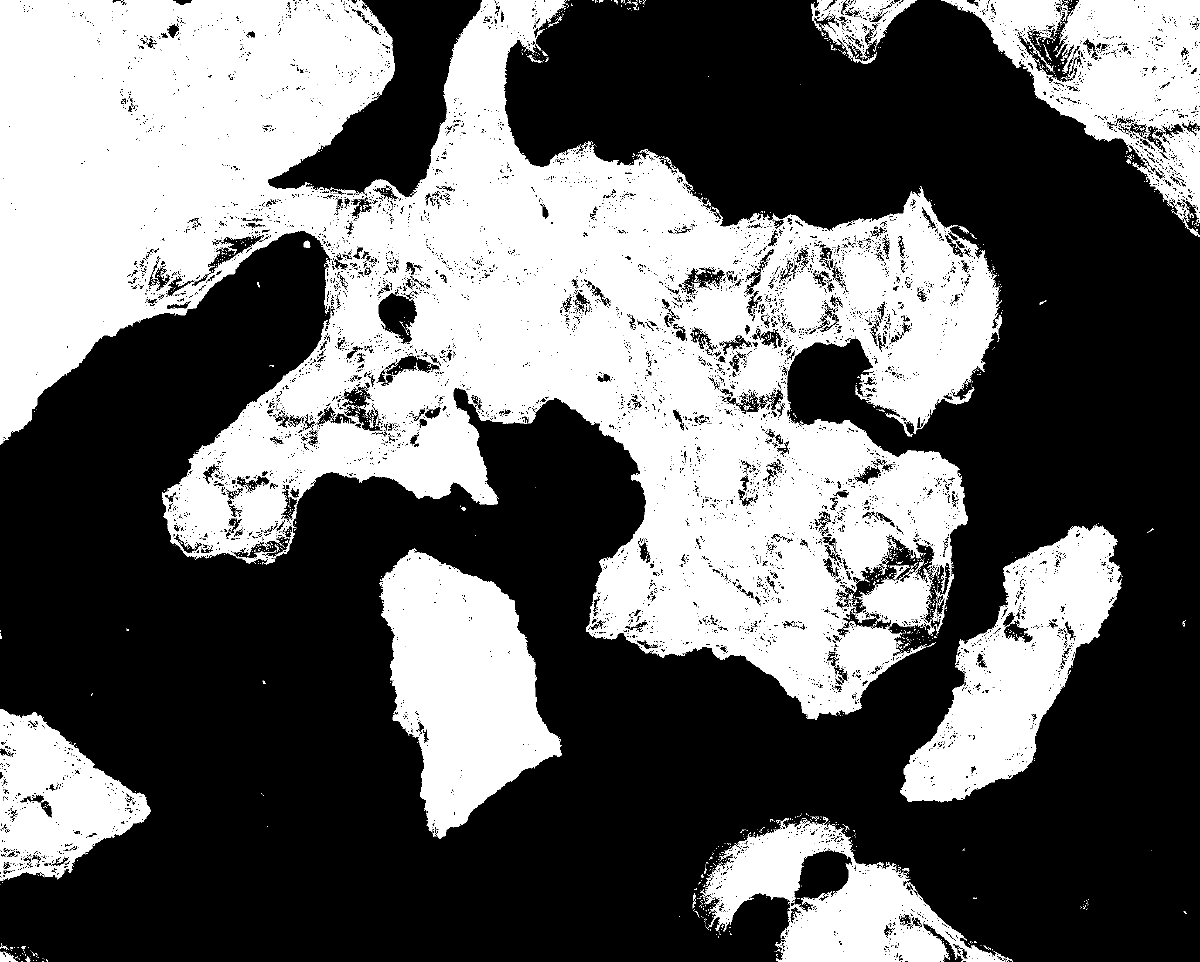

Fj Nuclei Segmentation Result 103 nuclei — Osteosarcoma_01.tif

103 nuclei detected · Approach #9